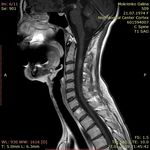

МРТ